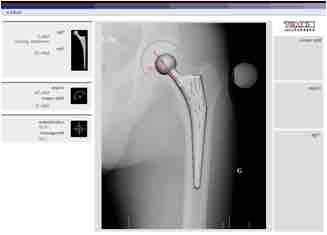

Planning Arthroplasty

CAD assisted planning for Total Hip Arthroplasty.

For the last 45 years, the most successful and common form of arthroplasty has been the surgical replacement of degenerated joint surfaces with prostheses. For example, a hip joint that is affected by osteoarthritis may be replaced entirely (total hip arthroplasty) with a prosthetic hip. This would involve replacing both the acetabulum (hip socket) and the head and neck of the femur. The purpose of this procedure is to relieve pain, to restore range of motion, and to improve walking ability; thus leading to the improvement of muscle strength.